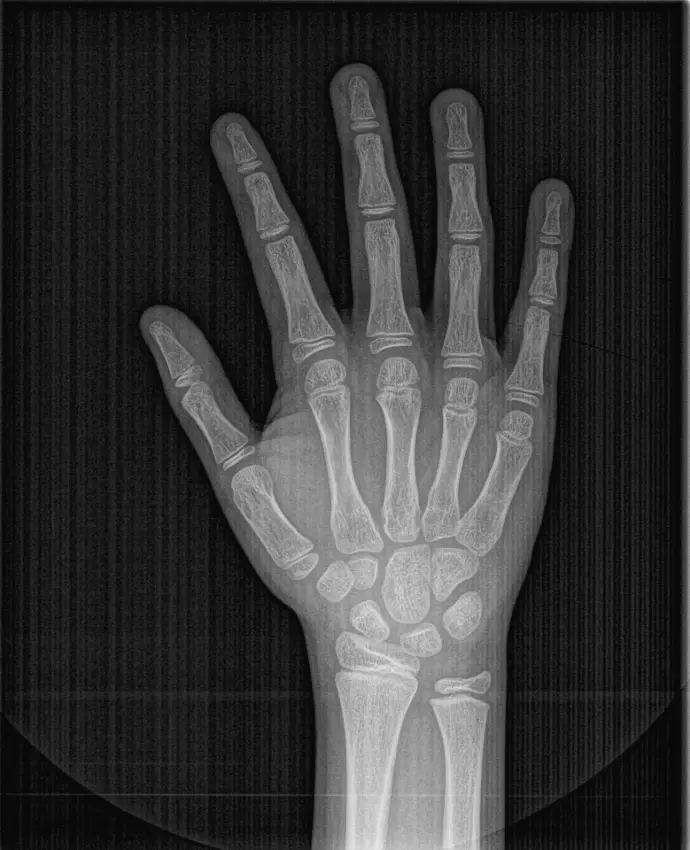

RX CARPAL

Permite obtener imágenes de la muñeca y los huesos del carpo, generalmente de la mano izquierda, con el fin de determinar el grado de maduración ósea y evaluar el crecimiento y desarrollo en niños y adolescentes